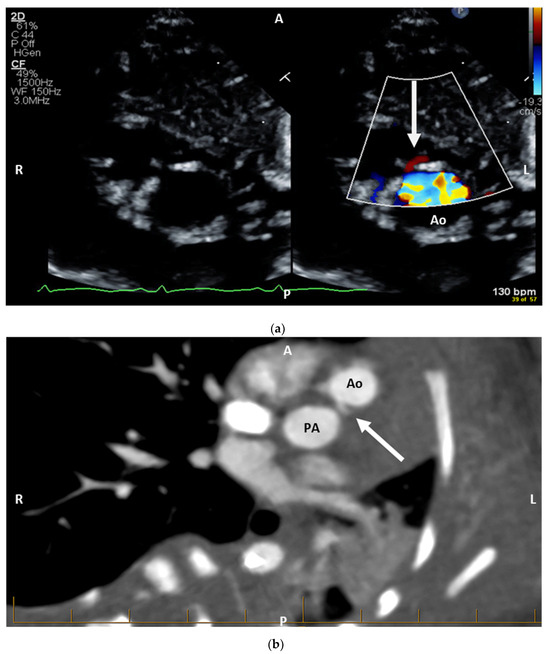

Figure 2. Salient postnatal imaging findings for Patient A. Focused diagnostic imaging in Patient A demonstrated both coronary systems originating from the right-facing sinus (2LCx*, R—Leiden convention for coronary anatomy) and intramural course of the left main coronary. (a) Trans-thoracic echocardiography demonstrating the left coronary artery as it originates off the right-facing sinus (arrow), with an intramural course as it travels through the intercoronary commissure. (b) CTA demonstrating the coronary arteries arise from separate origins off the posterior rightward-facing aortic cusp of the aorta, where the left coronary artery takes an intramural course (white arrow). Ao = aorta, PA = pulmonary artery, A = anterior, P = posterior, R = right, L = left.